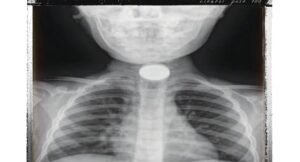

घटना के बाद बच्ची को लगातार तीन दिनों तक उल्टियां और गले में तेज दर्द की समस्या बनी रही। परिजन जब उसे जिला अस्पताल लेकर पहुंचे, तो विशेषज्ञ डॉक्टर अरविंद सिंह चौहान ने जांच के बाद तुरंत एक्स-रे कराने की सलाह दी। रिपोर्ट में गले के अंदर सिक्का फंसा होने की पुष्टि हुई।

स्थिति को गंभीर मानते हुए डॉक्टर चौहान ने बिना देर किए ऑपरेशन का निर्णय लिया। एनेस्थीसिया विशेषज्ञ डॉक्टर चेतन बमोरिया और स्टाफ नर्स रोशनी व गायत्री की टीम ने मिलकर प्रक्रिया को अंजाम दिया। महज 5 मिनट में सफल ऑपरेशन कर सिक्के को सुरक्षित बाहर निकाल लिया गया।